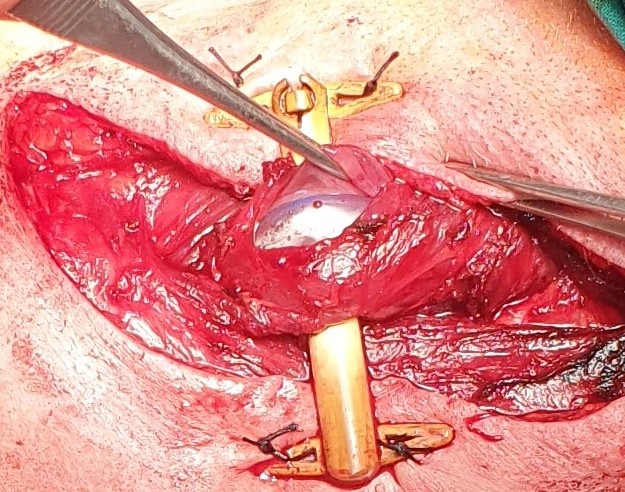

Οισοφαγοστομία. Αποκλεισμός κατώτερου οισοφάγου (Ευγενική παραχώρηση Dr. V. Penopoulos)